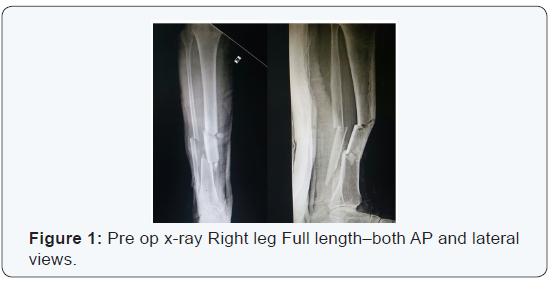

A 38 year old male presented to the casualty with history of RTA. He came to our institute with complaints of swelling of the right lower limb. There were no external wounds, but there were extensive grazed abrasions on the anterior aspect of right leg. His vitals were normal. No head injury or any other solid organ injury. Plain X-ray showed a Segmental fracture of both bone along with lateral condyle fracture of tibia (Figure 1). He was assessed for other co morbid conditions [4]. He was fit for the surgical procedure. He was taken up for surgery. Treated by closed reduction and internal fixation by using interlocking tibial nail. Fibula was fixed with a rush pin. Lateral condyle fracture of tibia was fixed with cannulated cancellous screw along with a washer. Post operative recovery was uneventful. Immediate post op x-ray showed a satisfactory reduction of fracture (Figure 2). Later he was put on non weight bearing of right leg for 6 weeks. Later x-ray was taken at 1 year post operative (Figure3).